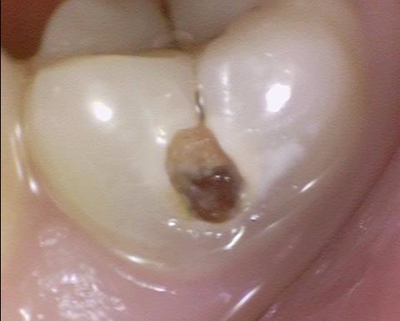

앞니 충치 파고파고 팠는데도 아직 남아있고 치아 다 없어질 정도만 남은거 실화인가요ㅠㅠ

그래도 살리기 위해 최대한 노력하여 임플란트 없이

살렸습니다...